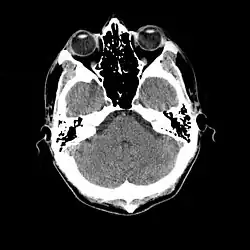

- Cranial computed tomography (CT, invented 1972) proved to be an excellent tool for diagnosing cerebral neoplasms in children, including those found in tuberous sclerosis.[46]

- MR was judged superior to CT imaging for both sensitivity and specificity. In a study of fifteen patients, it identified subependymal nodules projecting into the lateral ventricles in twelve patients, distortion of the normal cortical architecture in ten patients (corresponding to cortical tubers), dilated ventricles in five patients, and distinguished a known astrocytoma from benign subependymal nodules in one patient.[53]

- MR imaging was found to be capable of predicting the clinical severity of the disease (epilepsy and developmental delay). A study of 25 patients found a correlation with the number of cortical tubers identified. In contrast, CT was not a useful predictor, but was superior at identifying calcified lesions.[54]